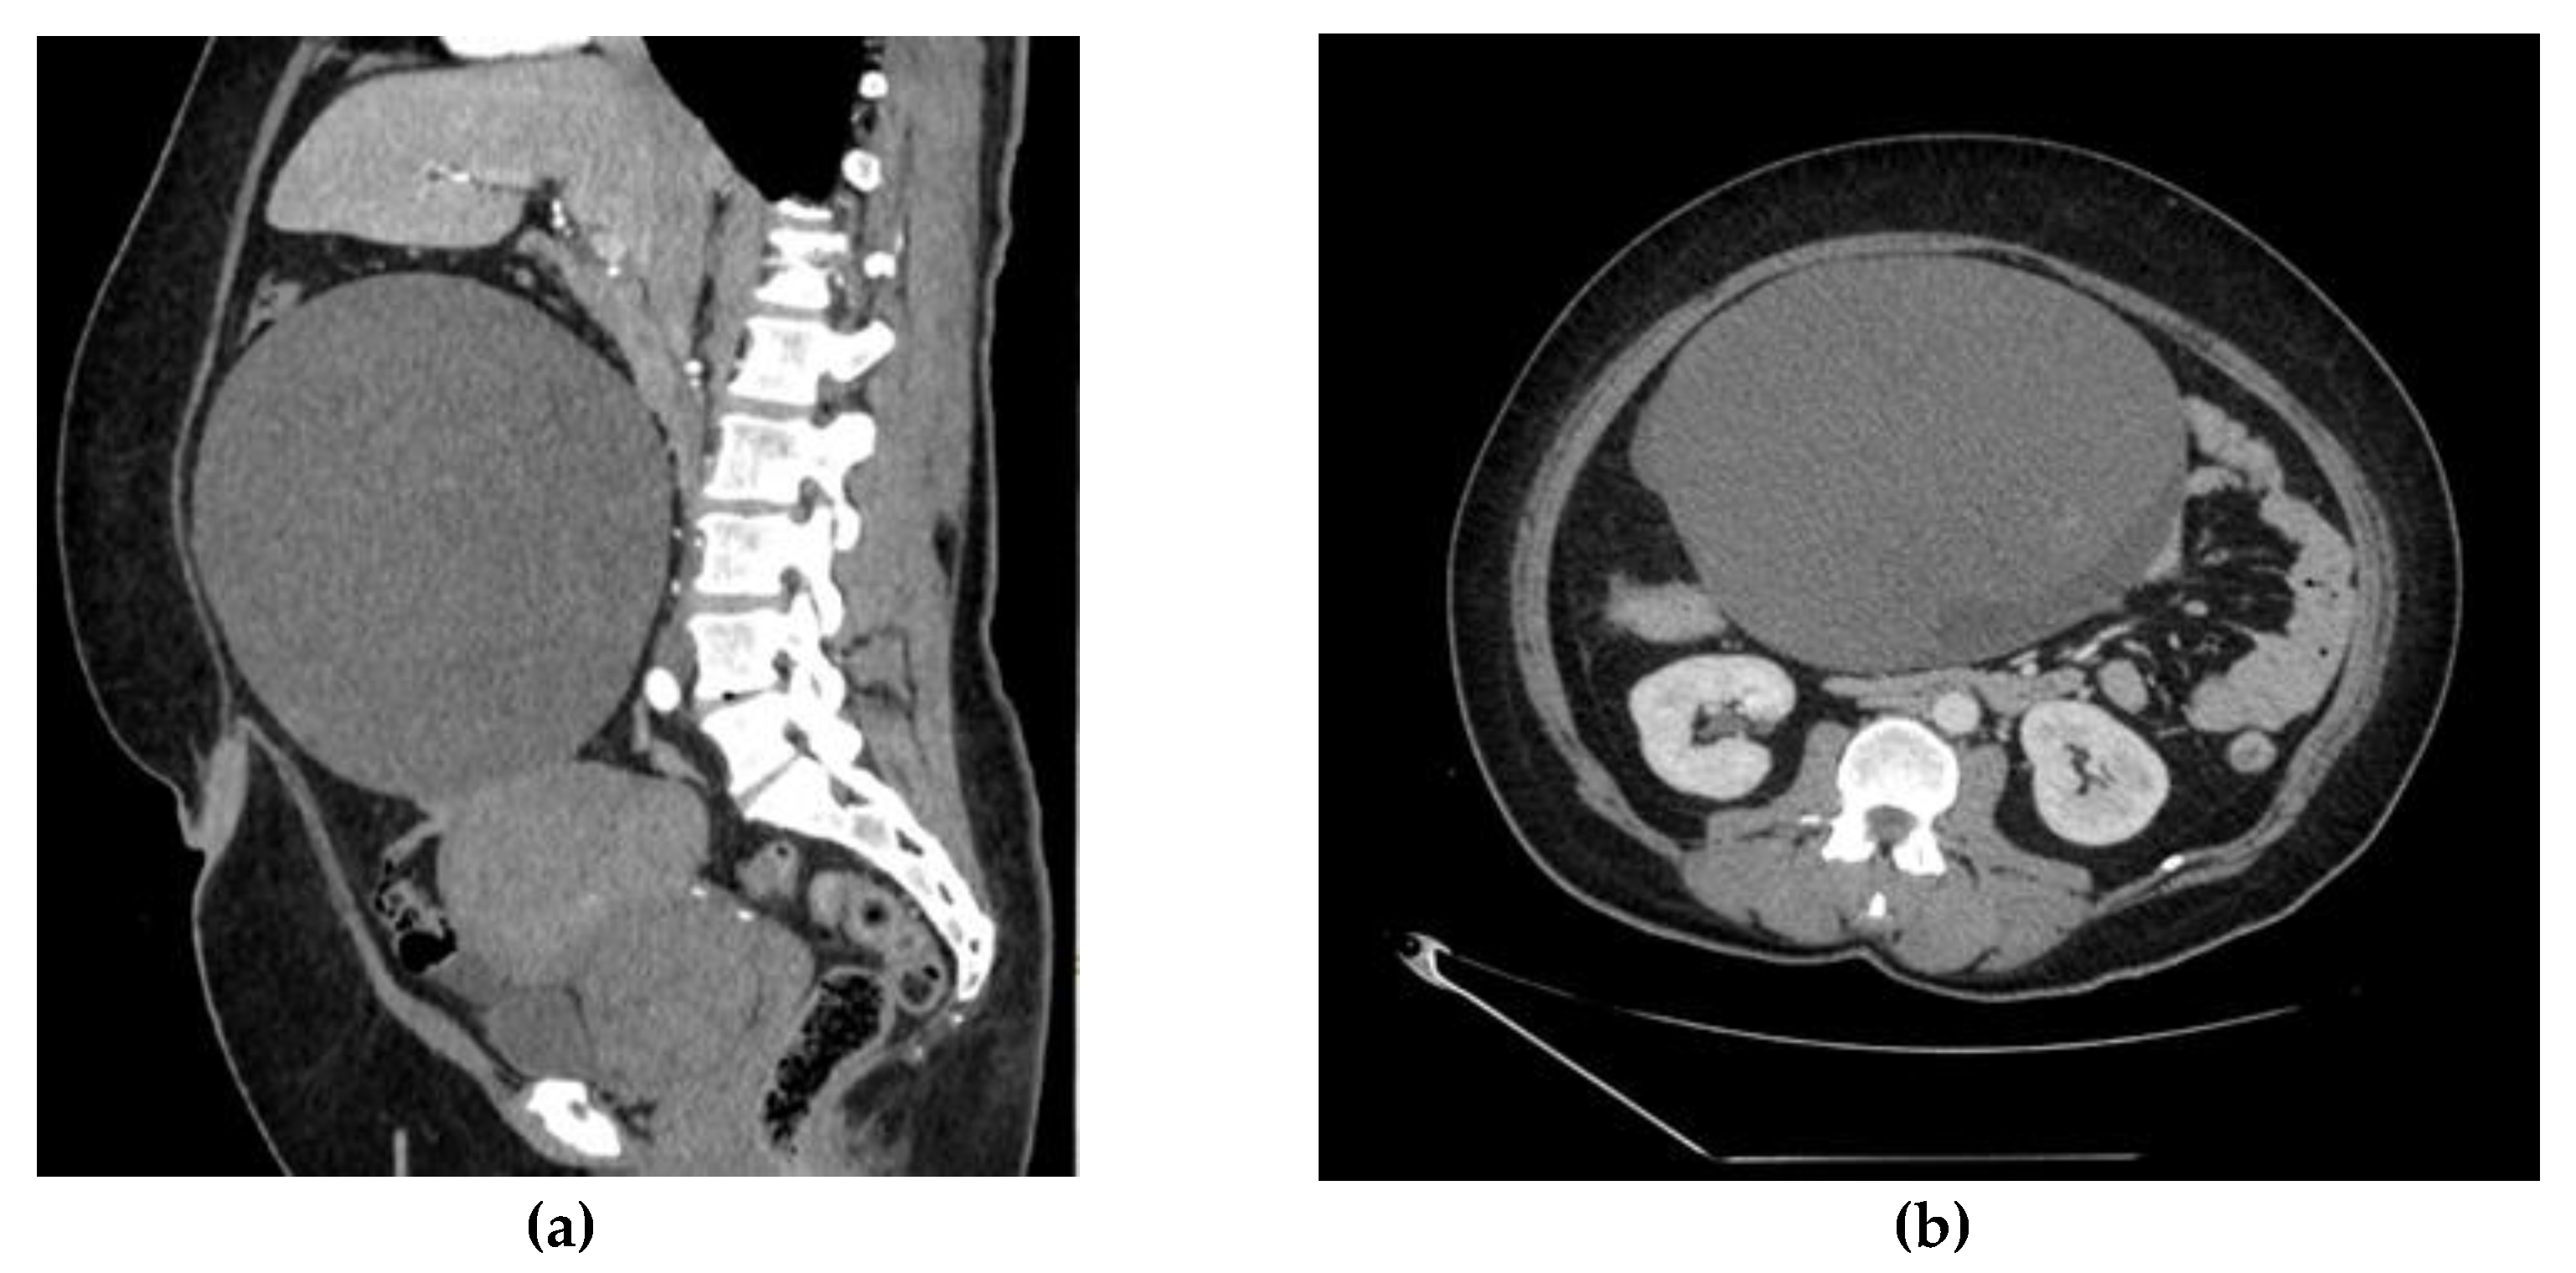

Abdominal CT scan was performed: an enlarged and deformed uterus with multiple uterine myomas was observed and a large (207 × 155 × 182 mm) thin-walled inhomogeneous tumor connected to the uterus and right ovary was found (Figure 1a,b). the enlarged and deformed uterus with multiple large intramural uterine myomas (about 6–7 cm), which caused prolonged and heavy menstrual bleeding, was the main cause of anemia.

Figure 1.

(a). Abdominal CT scan shows enlarged and deformed uterus, large (207 × 155 × 182 mm) thin-walled inhomogeneous tumor, connected to uterus and right ovary. (b). Abdominal CT scan shows multiple uterine myomas and a large (207 × 155 × 182 mm) thin-walled inhomogeneous tumor.

The content of the tumor was similar to hemorrhage. Active extravasation was not present, and a possible right adrenal gland adenoma was detected. A small amount of ascites was also observed.